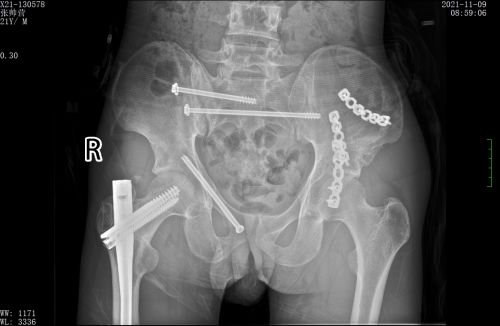

术前x线可见多处骨折。

术后,骨折断端固定牢靠。

创伤骨病科主任盛斌指出:患者骨盆存在多处骨折,失血性休克明显,由于此处解剖结构的复杂性和特殊性,传统手术方式往往手术时间长、创伤大、出血多。而如果不能早期对骨盆环进行稳定,骨折端及其他部位的静脉丛可反复出血,导致休克加重,危及生命。患者刚做了开腹手术,如果再进行传统骨折切开复位手术,风险极高。

经过反复讨论研究手术方案,在麻醉科、手术室的配合下,盛斌主任带领创伤救治团队为小张施行复杂骨盆及股骨骨折微创复位内固定手术。术后,在急诊ICU等多学科团队的积极治疗和精心护理下,患者病情好转出院。